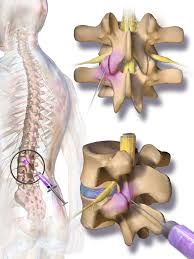

Epidural steroid injections are usually limited to just a few a year because there's a chance these drugs might weaken your spinal bones and nearby muscles. Cortisone injections may be given up to four times a year per affected joint. Cortisone injections can be helpful for patients with rheumatoid arthritis. 3 to improve the overall outcome of the procedure and reduce the risk of side effects, using a blunt needle, live fluoroscopy, and administering a small test dose initially may be helpful. Repeated cortisone injections are not healthy for tissues. This isn't caused by the needle — it's a possible side effect of steroids. For chronic conditions, three to six months or more between injections is common. No more than three cortisone shots in the space of a year is a typical number that many orthopedic surgeons use. Epidural steroid injections are recommended to be administered up to three to six times per year. Cortisone shots may be given for conditions such as tennis elbow. However, other experts believe that up to 6 injections per year is safe. In the case of a new disc herniation, injections may be only weeks apart with a goal of quick and complete resolution of symptoms. Medicare will cover epidural steroid injections as long as they're necessary.